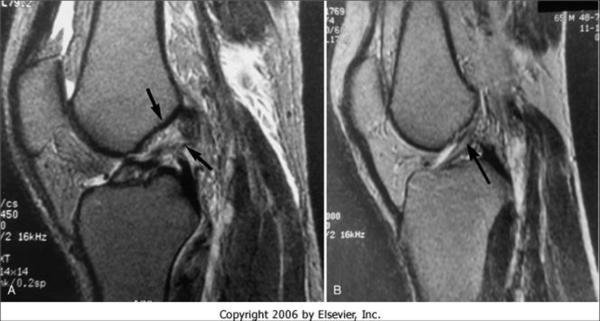

核磁表現(xiàn)

全斷裂

直接征象

1、連續(xù)性中斷(所有層面找不到一個(gè)完整的ACL)

2、韌帶增粗呈團(tuán)塊狀、 ACL內(nèi)形成假瘤,T1WI低信號(hào)、T2WI 高低混雜 見不到完整的纖維束。

3、邊緣不規(guī)則、成角扭曲呈波浪狀(MRI連續(xù)性未見中斷、鏡下用探子探察全斷)

4、T2WI彌漫性高信號(hào)

間接征象

1 、ACL與脛骨平臺(tái)夾角小于45度(松弛)(21%)

2 、外側(cè)脛骨平臺(tái)、股骨外髁挫傷(對(duì)口吻)或骨、軟骨骨折(撕脫骨折)。

3、 PCL角度小于107度, PCL弧度大于0.39

4、 脛骨前移大于7mm

5、外側(cè)半月板后移

ACL部分撕裂表現(xiàn)

1、信號(hào)增高 T1 T2均可見,仍可見連續(xù)性完整的纖維束

2、 ACL變細(xì)

3 、某個(gè)序列中見到ACL撕裂的間接征象,而在另一個(gè)序列中見到完整的ACL。

慢性損傷

出血、水腫消退,同時(shí)由于纖維癖痕的橋接有時(shí)可與正常相似,或僅表現(xiàn)為韌帶輪廓、走行的異常(如韌帶的增粗不規(guī)則、成角等,而韌帶信號(hào)常無異常)。鄰近組織內(nèi)有無水腫是鑒別急慢性 損傷的主要依據(jù)